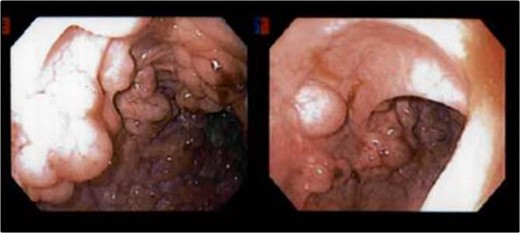

Multiple submucosal air pockets (cysts) ranging in size from 0.3 to 1.5 cm.